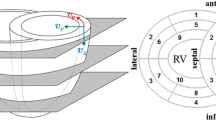

Figure 1 exemplarily shows anatomical and velocity encoded images of the myocardium acquired without and with k-t BLAST acceleration applying acceleration factors of two, four and six. All data were acquired approximately 50 ms after the R-Wave. For low k-t BLAST acceleration factors, the anatomical and phase encoded images do not show obvious deterioration. With increasing k-t BLAST factors, however, an increasing blurring can be observed in the anatomical images. In the TPM data, a reduction of velocity amplitude with increasing k-t BLAST factors can be noticed.

Anatomical and phase contrast images with and without k-t BLAST. Anatomical (left) images of the myocardium and respective velocity encoded phase images in AP, FH and RL directions for the conventional sequence and the k-t BLAST accelerated sequences (acceleration factors 2, 4 and 6, heart phase with maximum longitudinal velocity (approx. 50 ms after the R-Wave)